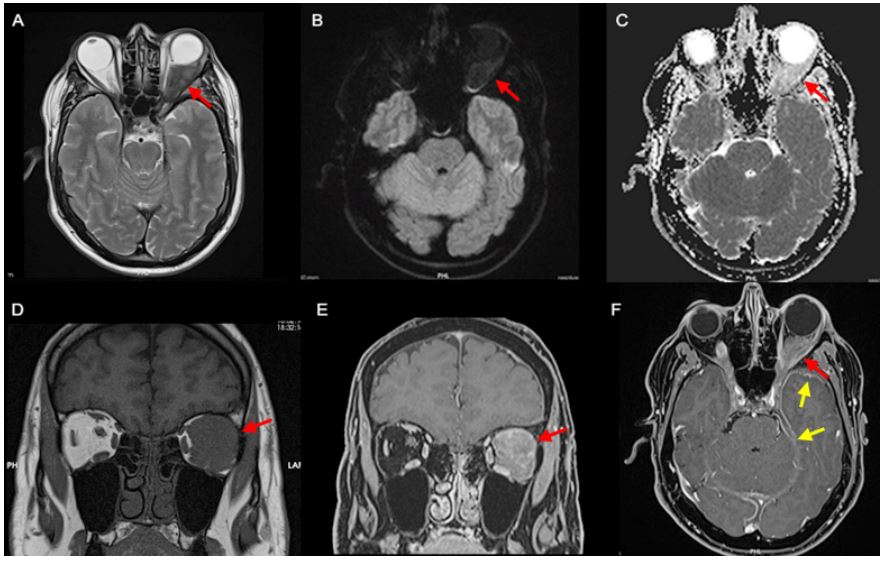

A 58-year-old man with a medical history of hypertension, controlled with candesartan and hydrochlorothiazide, and surgical history of left eye cataract surgery using retrobulbar anesthesia 1 month prior presented with complaints of blurry vision and headaches since the surgery. Ophthalmologic examination revealed left proptosis, chemosis and limitation of upwards and downwards eye gaze, without diplopia. A central scotoma and hyporeactive left pupil were also documented without clear relative afferent pupillary defect. Routine laboratory results were unremarkable. Urinalysis did not show proteinuria or hematuria. Computer Tomography (CT) (Figure 1) and Magnetic Resonance Imaging (MRI) (Figure 2) were performed that revealed a left intraorbital infiltrating soft tissue lesion with involvement of the superior and lateral rectus muscles and extension into the preseptal space, involving and enlarging the lacrimal gland. The lesion displaced the left optic nerve medially and the globe inferiorly. A right infiltrating orbital apex lesion with similar imaging characteristics was also documented. Intracranially, temporal and tentorial pachymeningeal thickening was also noted.

Figure 2: MRI depicting a left orbital retrobulbar mass hypointense on T2-weighted imaging due to its fibrous nature (A), without restriction on diffusion-weighted imaging (B and C) and spontaneously hypointense on T1-weighted imaging (D) with strong homogeneous enhancement depicted on the fat saturated post-contrast T1-weighted images (E and F) (red arrow). The lesion involved the left lateral and superior rectus muscles, with anterolateral extension to the ipsilateral lacrimal gland and posterior extension to the cavernous sinus. A smaller soft tissue enhancing lesion was also documented in the right orbital apex with extension to the right cavernous sinus, with the same signal characteristics and, intracranially, left-predominant bilateral temporal and tentorial pachymeningeal thickening was better depicted (F; yellow arrow).